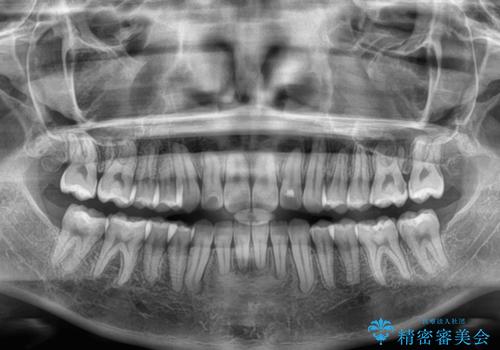

僅か8ヶ月という短期間で、綺麗な歯列に仕上がりました。